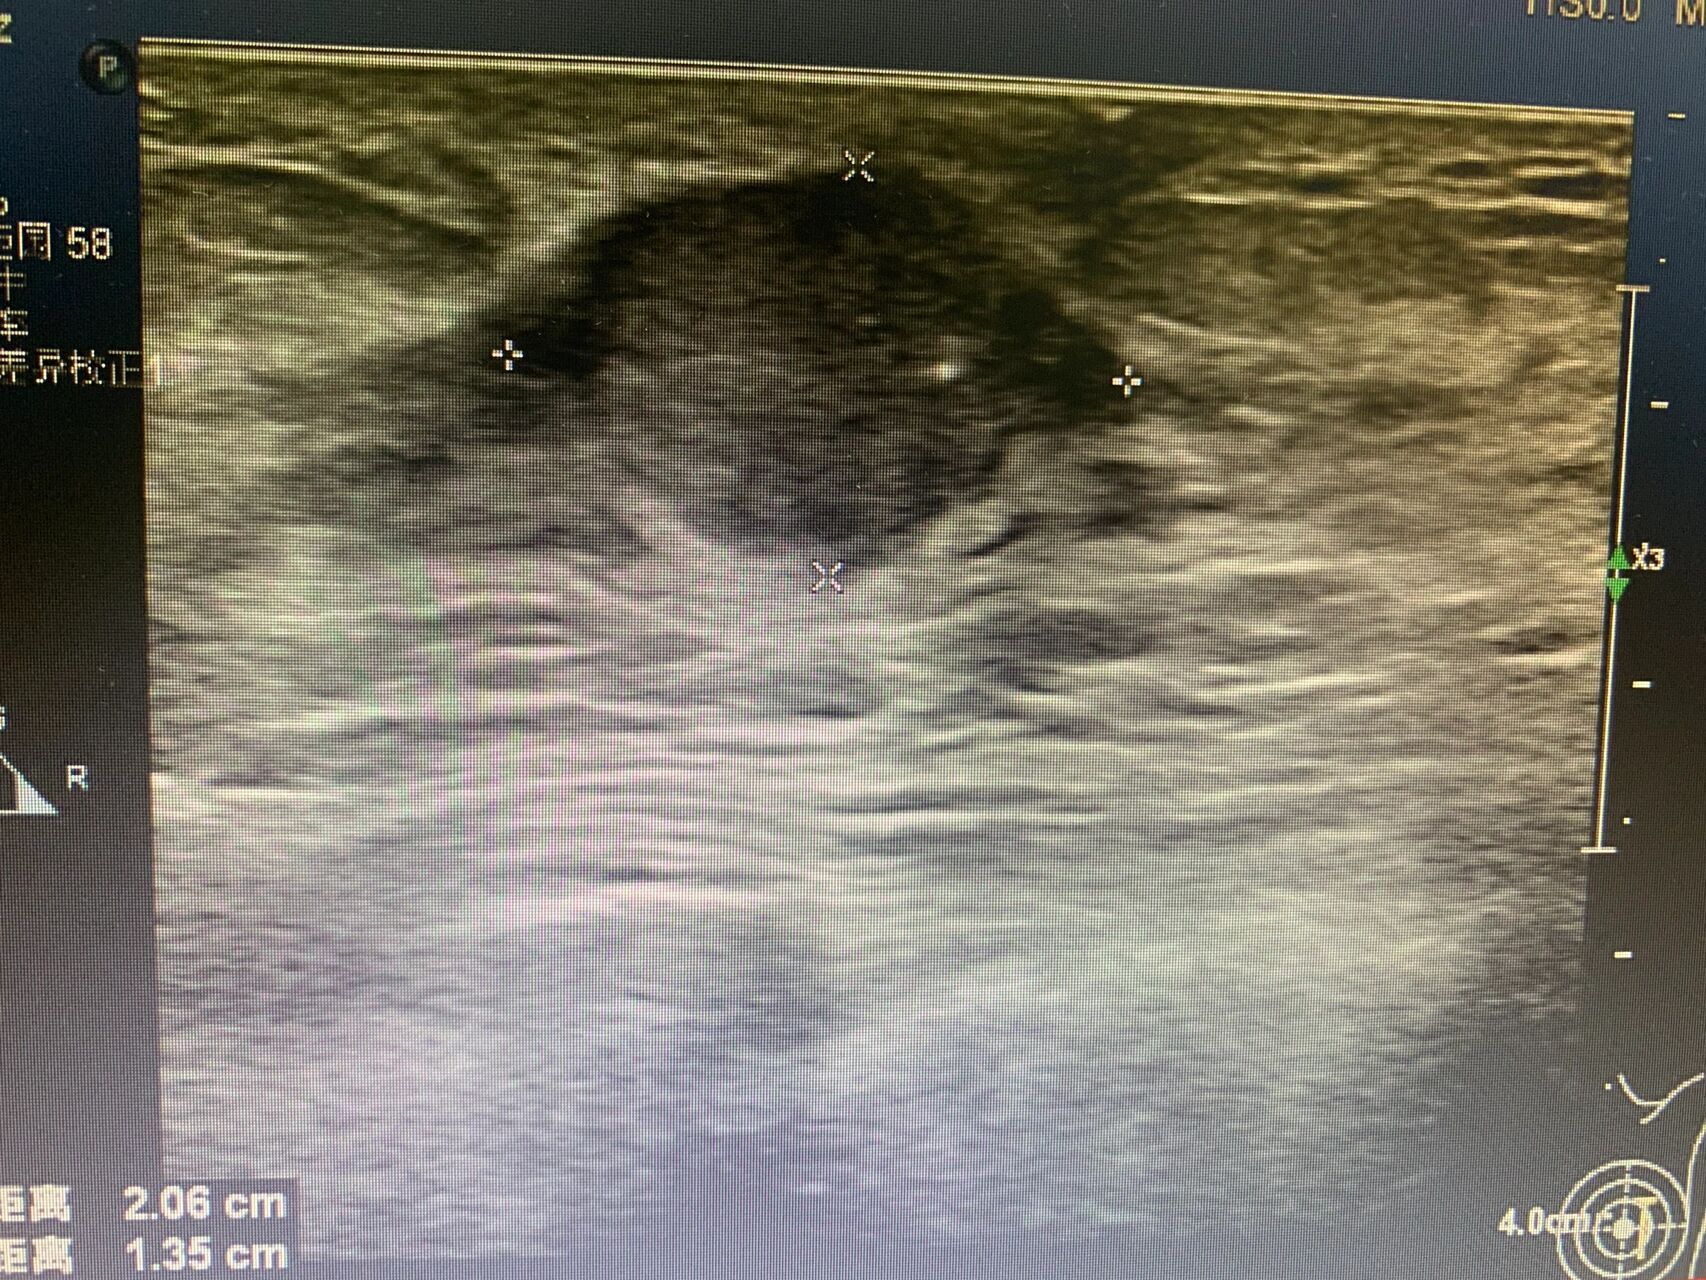

左乳腺肿物 浸润性癌讨论病例2019.4.